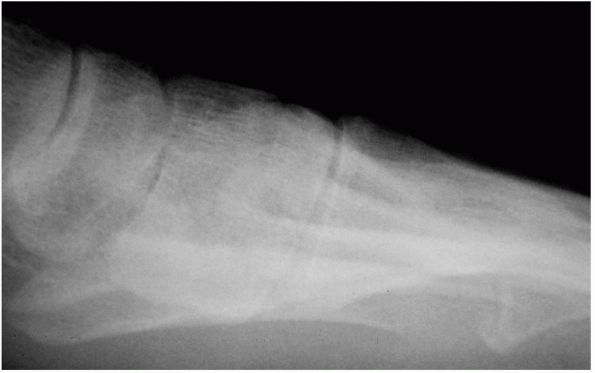

characteristic, demonstrating degenerative arthritis of the

metatarsophalangeal joint on the anteroposterior (AP) view. Besides the

narrowing of the joint, significant osteophyte formation is often

present along the lateral aspect of the joint. Medially, there rarely

is significant osteophyte formation. On the lateral view, there is a

dorsal osteophyte of varying degrees. Occasionally, there is an

osteophyte on the dorsal aspect of the proximal phalanx as well. In

advanced stages, the entire joint space may be compromised. This

continuum of disease has been staged as follows:

![]() |

FIGURE 21-9. (A and B)

First metatarsophalangeal joint in a patient with hallux rigidus. Note the increased bulk of the joint and marked osteophyte formation. (C) Lateral radiograph of a patient with hallux rigidus, with a large dorsal osteophyte that mechanically blocks dorsiflexion of the proximal phalanx. |